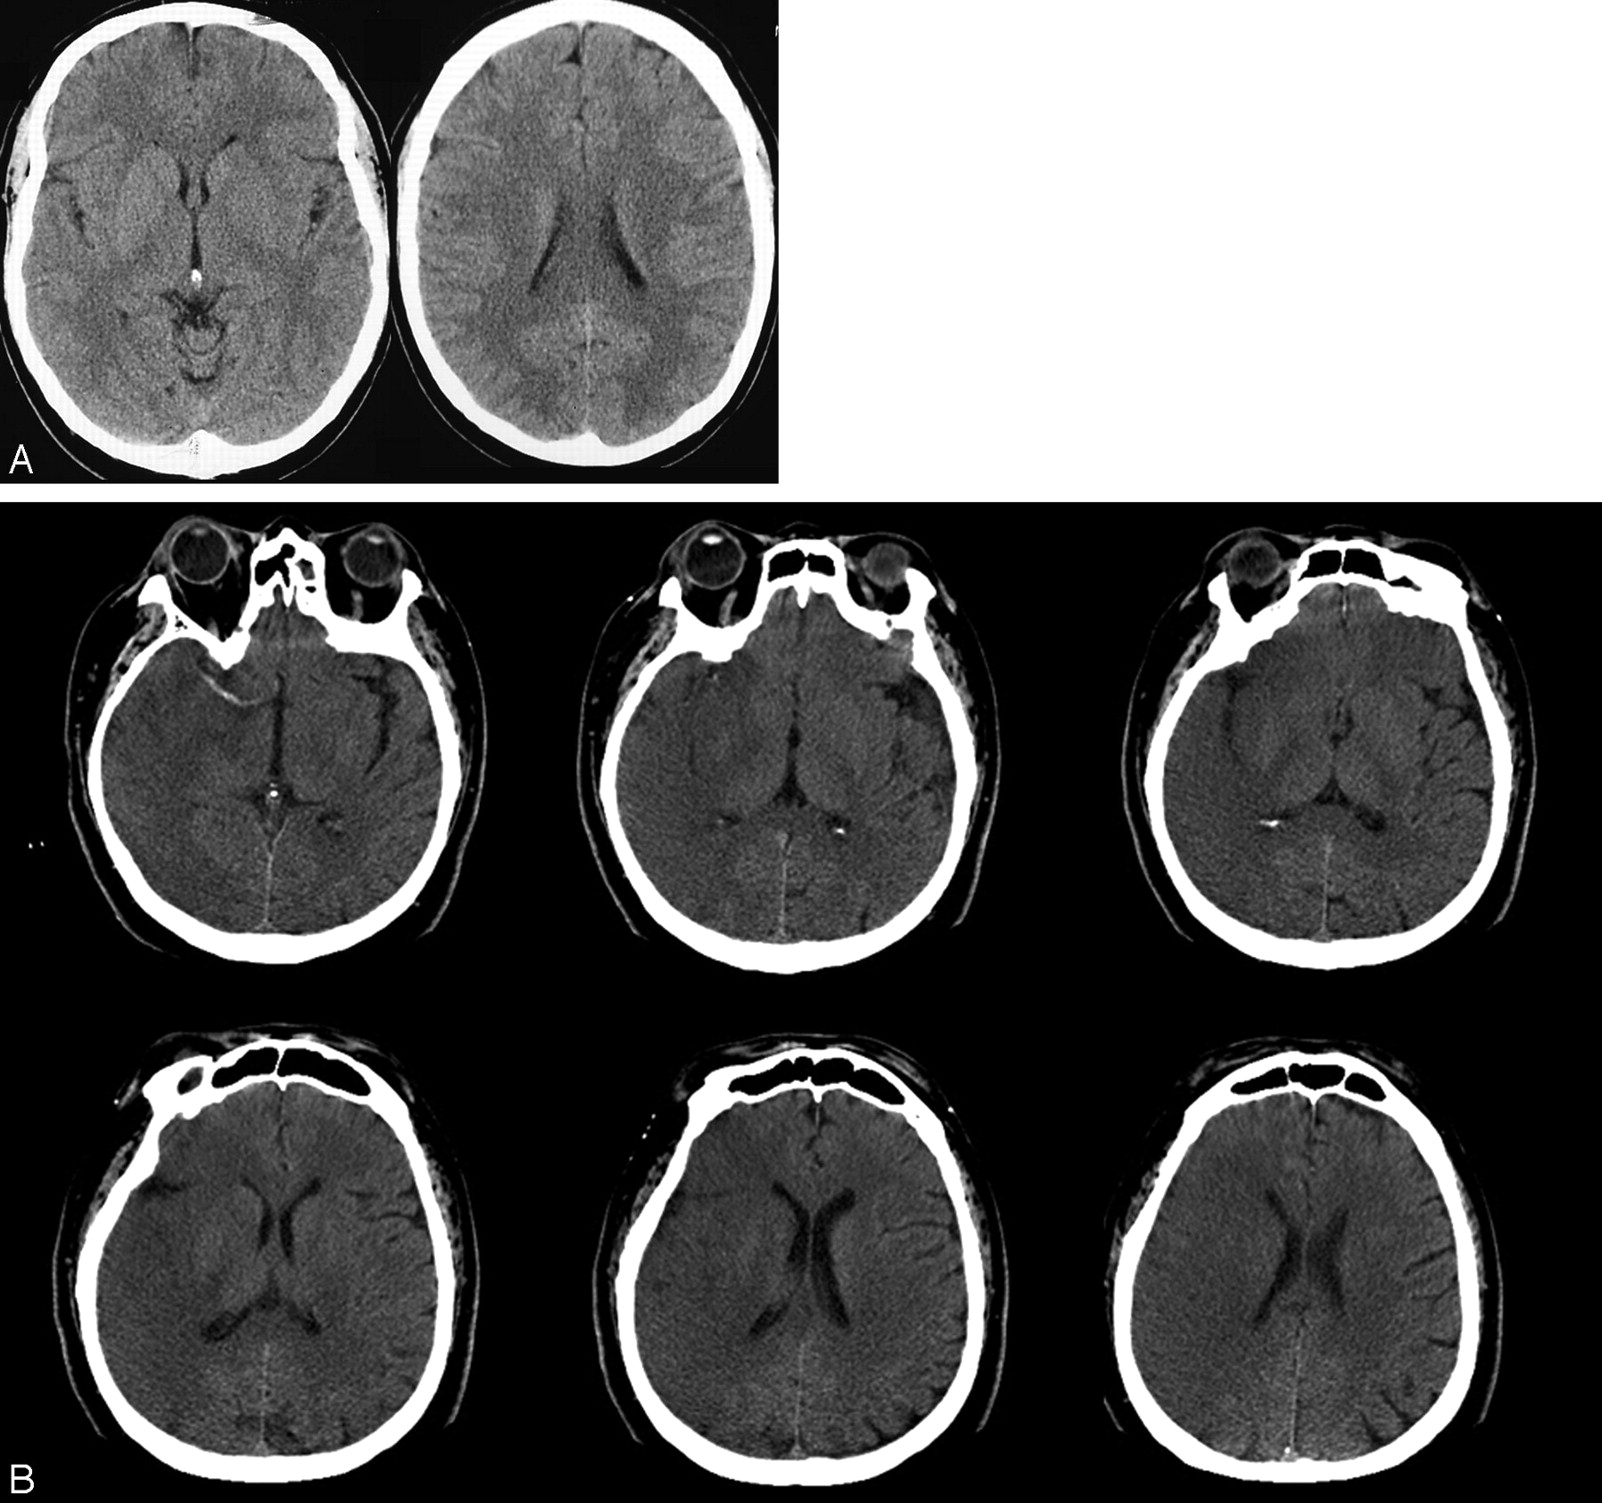

A, Baseline CT scan at 100 minutes from stroke onset showing a left middle cerebral artery infarct with an ASPECT score of 8. Points are taken off for hypoattenuation of the head of caudate and the lentiform nuclei. Based upon our data, this patient would be an ideal candidate for IV-IA therapy.

B, Baseline CT scan at 175 minutes from stroke onset showing a well-evolved right middle cerebral artery infarct with an ASPECT score of 0. Based upon our data, this patient could be harmed by IV-IA therapy.